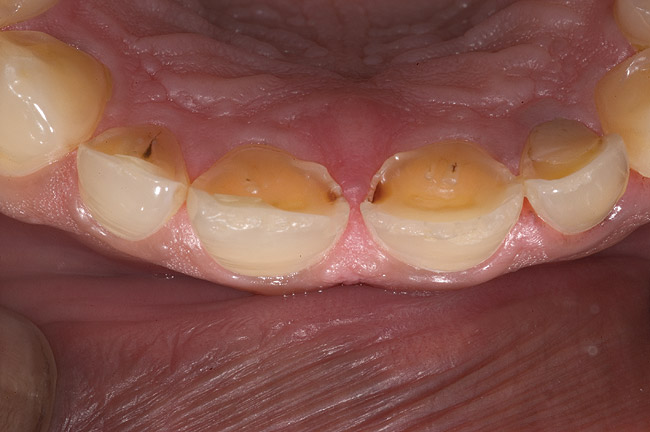

Acid dissolves the palatal enamel of upper anteriors, thus exposing the underlying dentin. This makes teeth appear higher in chroma and leads to hypersensitivity as well as supraeruption of opposing incisors. Clinically, this restricts the space needed to restore lost palatal tooth structure (Figure 1 and Figure 2).

Figure 6  1:1 view demonstrating severe loss of tooth structure due to palatal erosion.

Figure 6

Figure 7  Palatal surface showing loss of form due to enamel dissolution.

Figure 7